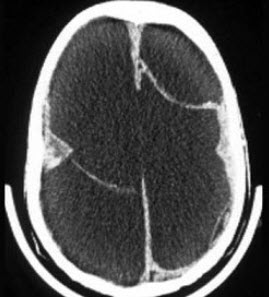

九个月男孩,头明显增大,前囟大而且鼓出,头下垂,双眼有落日征,头部叩诊有破壶音。四肢活动少,双侧Babinski征阴性,体温正常。

(单选题)根据CT表现可能的诊断( )

A:先天性脑积水